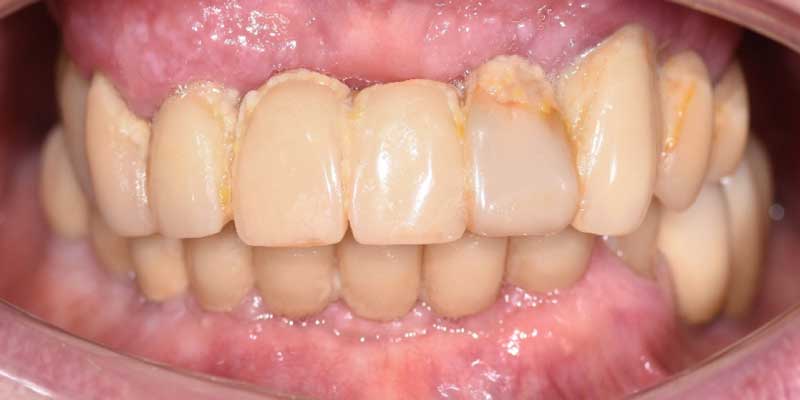

Subito dopo il posizionamento degli impianti, il dentista fissa una protesi, realizzata già in fase di progettazione e che testimonia la precisione della pianificazione. Questa permette al paziente di masticare subito dopo l’intervento. Questi denti provvisori sono progettati per essere funzionali e stabili.

Aspetto della protesi prima dell’intervento